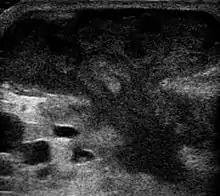

Ultrasound showing an abscess of the skin[21]

Ultrasound image of breast abscess, appearing as a mushroom-shaped dark (hypoechoic) area

An abscess is a localized collection of pus (purulent inflammatory tissue) caused by suppuration buried in a tissue, an organ, or a confined space, lined by the pyogenic membrane.[22] Ultrasound imaging in the emergency department can help in a diagnosis.[23] It is; however, more useful to rule out than rule in an abscess.[24]